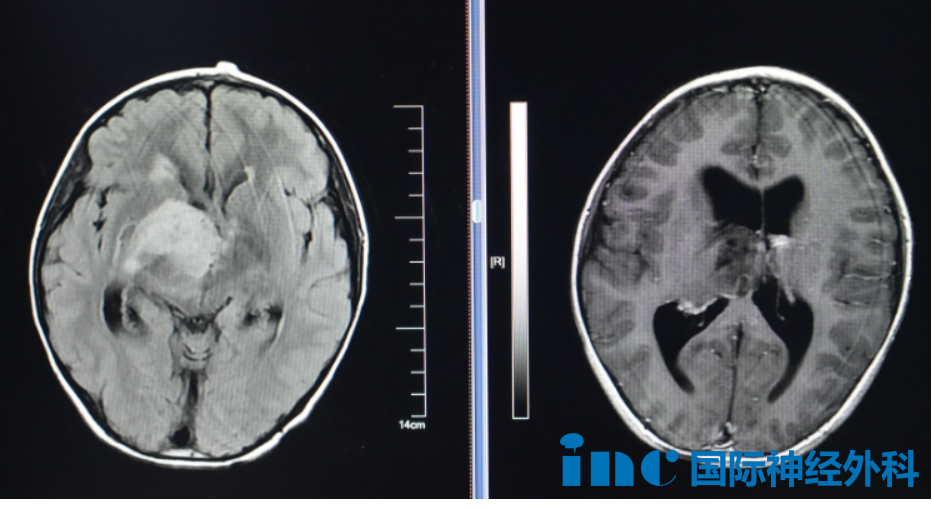

正式抵达苏州大学附属儿童医院的巴教授步履不停,今天他要去见一位小朋友——8岁的脑瘤患儿小航,终于等来了巴教授的示范手术。一个尺寸约达4.0cm×4.7cm×4.8cm的病灶,正盘踞在孩子右侧丘脑区域,并已引发脑积水。

弥散张量成像(DTI)是当前能有效观察和追踪脑白质纤维束的非侵入性检查方法,能够立体、直观地显示纤维束的走形变化,帮助术者进行手术。因此,为了保护孩子的运动功能,巴教授建议术前进行DTI重建,图像会显示出运动纤维与肿瘤的关系。这样主刀在手术时就能更加小心,避免误伤到它们。